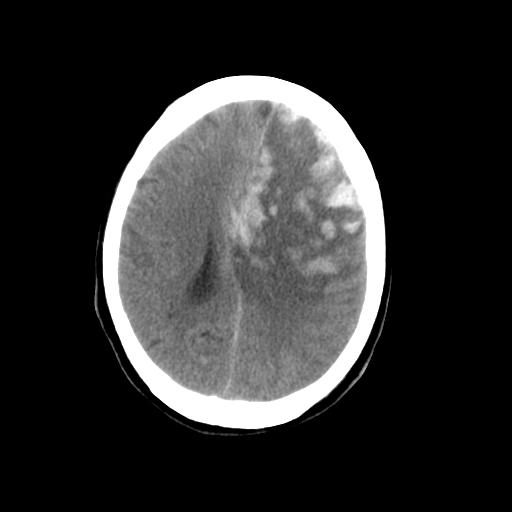

男,78岁。自诉两周前因右侧肢体障碍行ct检查,诊断为脑梗塞(患者ct片已丢失)治疗好转后出院。现因意不清12小时,又行ct检查。

结合病史考虑左侧额颞顶叶出血性脑梗塞。

结合病史考虑左侧额颞顶叶出血性脑梗塞